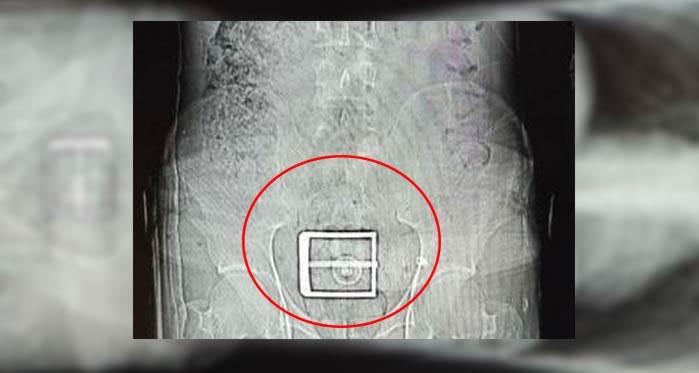

Edinilen bilgiye göre, Narkotik Suçlarla Mücadele ekiplerinin madde ticareti ve nakline yönelik yapılan çalışmalar sonucunda durumundan şüphelenilerek yakalanan ve uyuşturucu maddeleri yutarak nakletmeye çalışan İran uyruklu F.S. (30) yapılan iç beden muayeneleri sonucunda mide ve bağırsak kısmında 78 kapsül halinde 603,35 gr Afyon Sakızı ve 17 kapsül halinde 111,35 gr Metamfetamin maddeleri ele geçirildi.